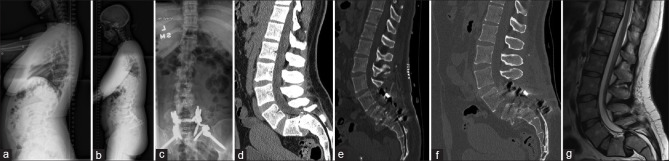

High-grade spondylolisthesis (HGS) remains a difficult entity to treat, given the high rate of complications following surgical correction of such a spinal deformity. Reduction of spondylolisthesis may be associated with traction injury to the L5 nerve root due to stretching. We report on two cases of HGS where a novel surgical technique of offset rods was used for partial reduction of spondylolisthesis thereby reducing L5 nerve root traction. Both cases had more than 50% correction of translation with good correction of slip angle and satisfactory clinical outcomes were achieved at the final follow-up. In this study, we report on two cases of HGS treated with offset rod constructs. These rod constructs provide partial reduction, improving slip angle at the listhesis while reducing nerve root stress caused by full reduction and fixation. In comparison to previously described constructs, offset rods provide greater construct modularity and freedom to create constructs better suited to each patient's pathology.